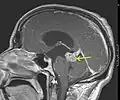

En début d'évolution, l'imagerie montre une tumeur isodense au scanner, d'où l'intérêt de l'IRM, plus sensible au dépistage de cette tumeur peu vascularisée. Lors de l'évolution, le scanner montre une tumeur hypodense, ne prenant généralement pas le produit de contraste. Il n'est pas retrouvé d'effet de masse puisque la tumeur est infiltrante.